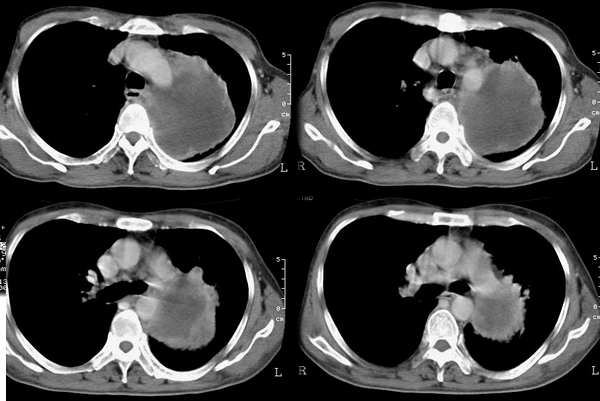

以下是引用乡医在2006-5-15 11:05:00的发言:[br]定位:来自纵隔[br]影象:与纵隔关系密切,类圆形,有膨胀感,有完整的壁及壁结节强化,内部密度均匀。[br]临床:男,60,胸不适半年,近有发热,无咳嗽咳血,平素体健无体检史。[br]影象意见:支气管囊肿合并感染。建议病理确诊。

以下是引用逸风在2006-5-15 17:08:00的发言:[br]ct所见各位老师描述很全面,不再赘述.补充一点,右侧镉肌局限性升高.[br]定位:左后上纵隔.从平片看,肿块外缘肺纹理呈弧形受压改变.横断扫描肿块在肺门周围靠后,肺门及气管位置未见明显移位.外周肺野未见明显阻塞性改变.[br]定性:恶性可能大.肿块边缘不光整,可见强化壁结节,内部有轻度不均匀强化密度,部分层面肿块与主动脉分界不清.右肺中叶小结节影.[br]诊断意见:左侧后上纵隔囊实性占位,考虑来源于神经源性肿瘤,恶性可能大.[br]建议:1.穿刺活检,明确诊断.2.b超右膈下检查,排外膈下病变.